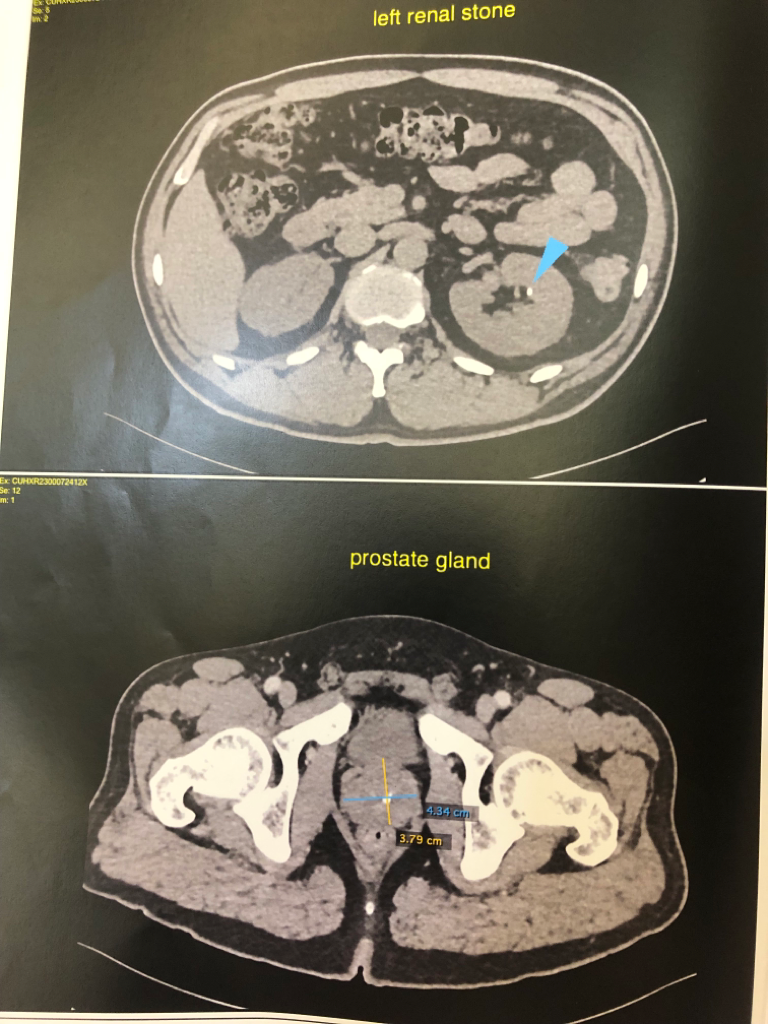

양쪽 부신에 낭종이 있고, 신장에 결석인지 물혹인지가 있고 폐 석회화,경증의 전립선 비대 등등이 있다고 알고 있는데요

• 3번 째 사진

• 4번 째 사진